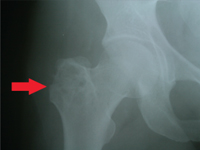

Diagnosis of disorders of the bone tissue, thanks to the availability of modern imaging methods, standardizes therapeutic management. The key element in the treatment of a patient diagnosed with a solitary bone cyst{index{solitary bone cyst} is to fill the defect in the structure with possible restoration of its function. The treatment of choice is autogenous or allogeneic bone grafting with the consequences and risks discussed later in the aticle.